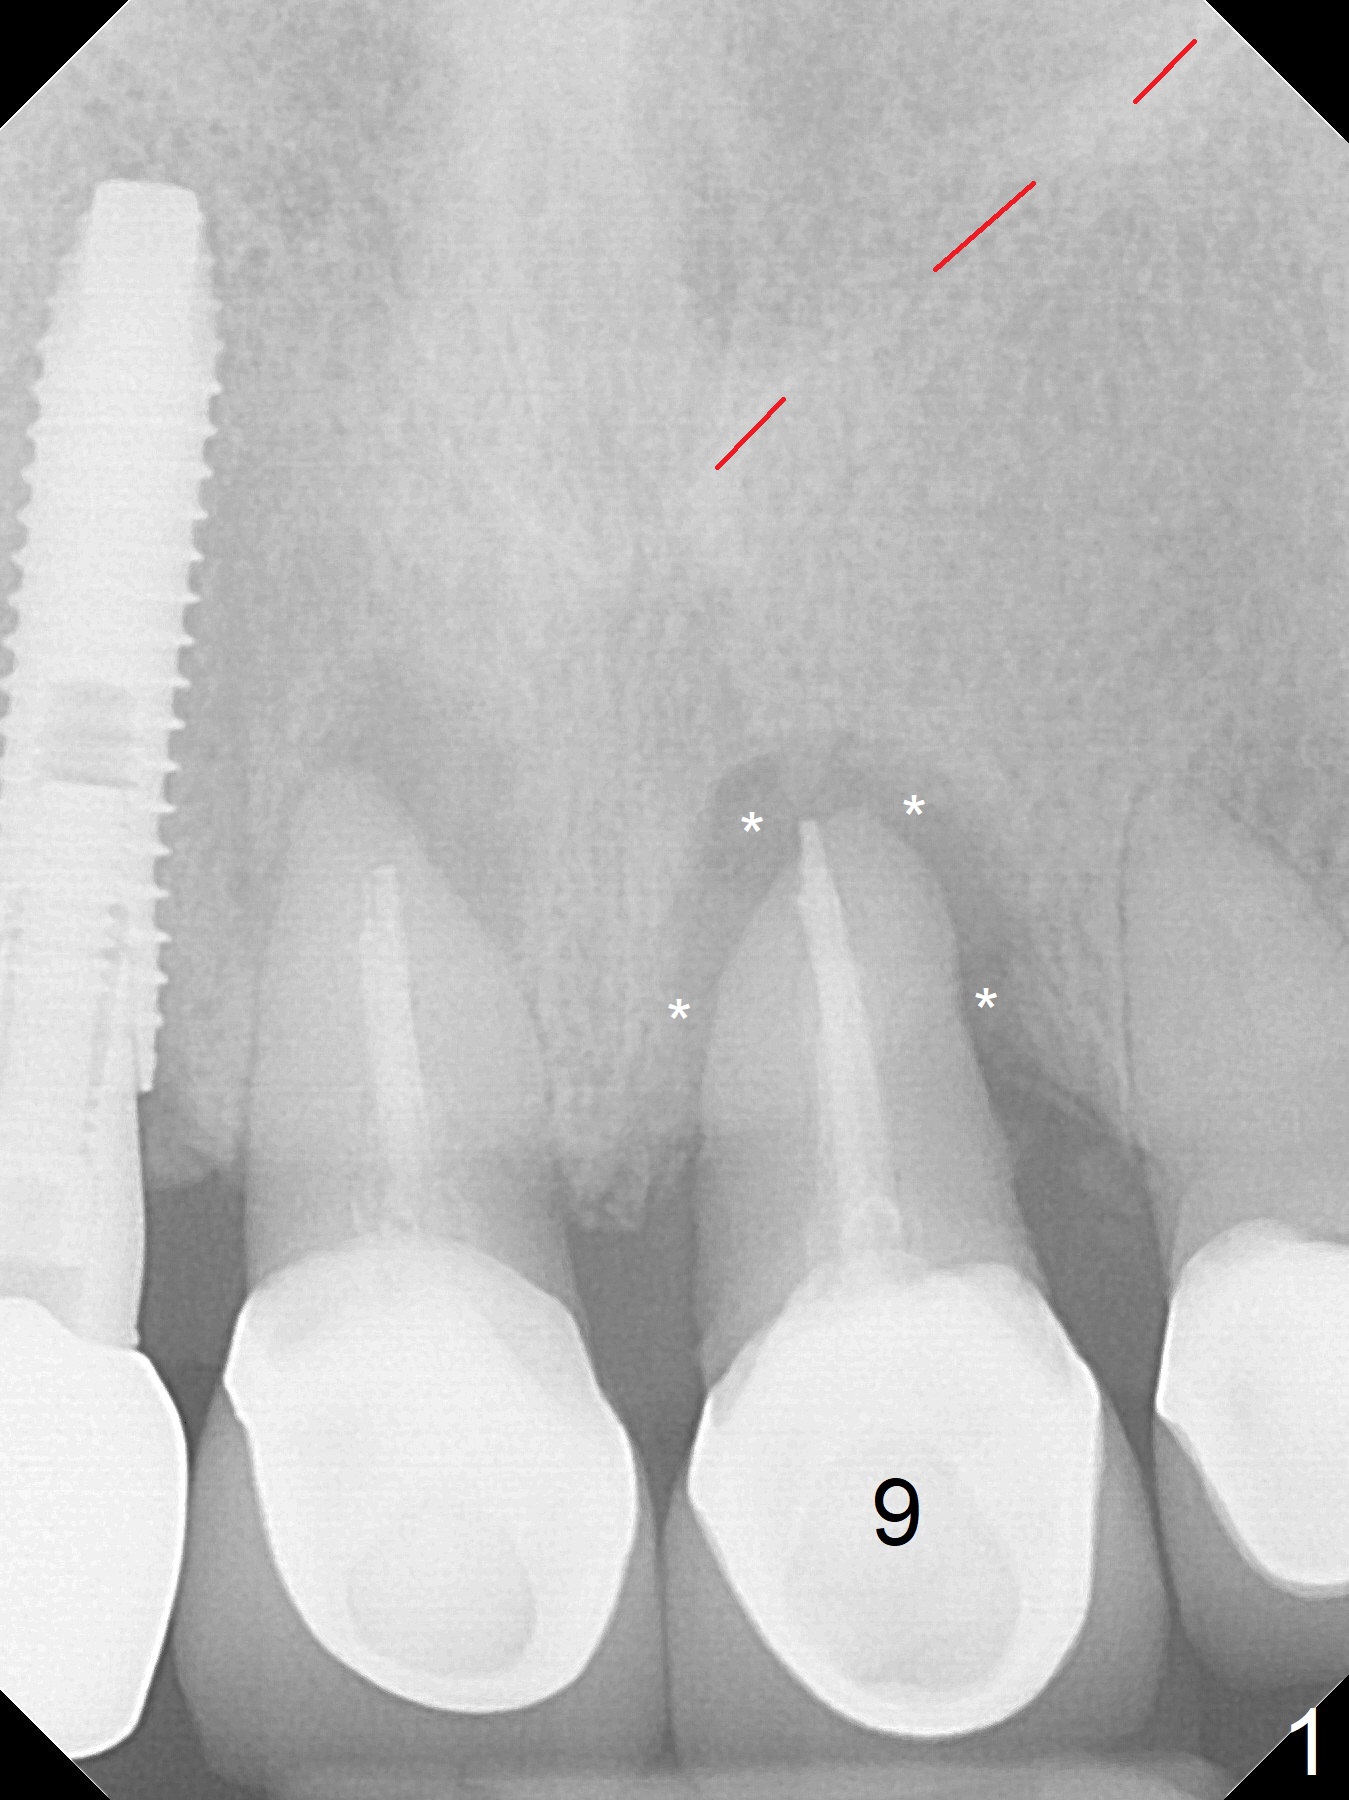

A 61-year-old woman returns with chief complaint of "loose tooth" at #9 nine month post cementation at #7 (Fig.1 (periradicular radiolucency (*)). Because of lack of posterior support, a long implant will be placed immediately post extraction (Fig.2). Be careful of the nasal floor, which is slanted (Fig.1 red dashed line). It seems that the implant at the central incisor would be shorter than that at the lateral one. The diameter should be the same. Take PA after 2 mm drill to avoid the Incisive Foramen (Fig.2 blue dashed line).